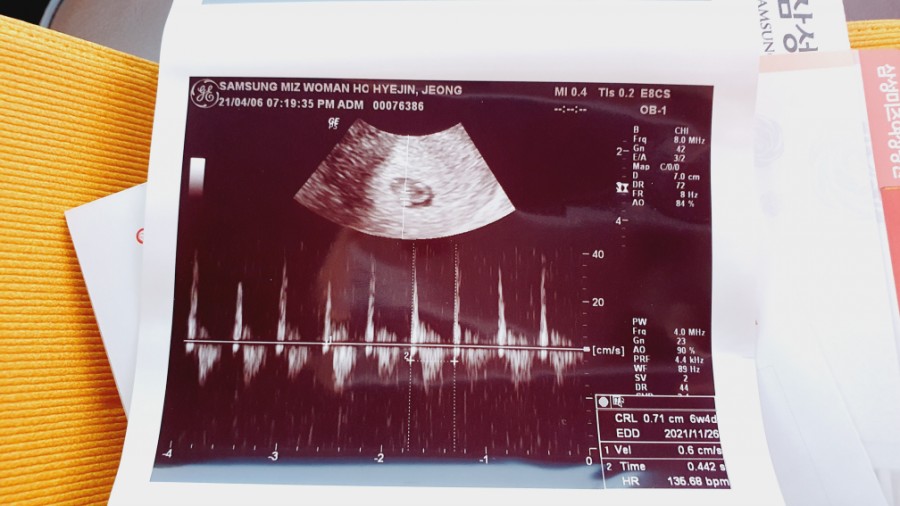

임신 6주 차 아기의 심장 소리를 듣고 신기하고 가슴이 뜨거워졌다.신기하다 심장 소리를 흘려도 아직 내 안에 아기가 있다는 게 실감이 안 나나중에 얘가 동그랗게 될 거라고 생각하니 그것도 신기하네.

심장 소리를 듣고 산전 검사를 했다